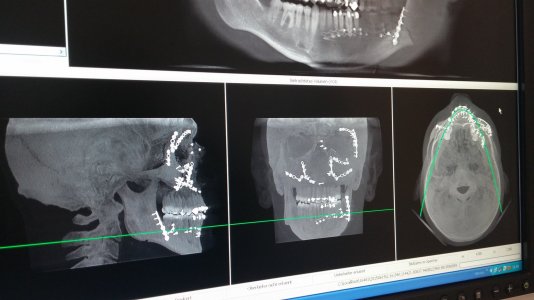

Gute Besserung wünsche ich dir. Und Kopf hoch es geht immer schlimmer. Meins bleibt definitiv drin. Und schrauben hab ich erst gar nicht angefangen zu zählen... Ja das bin ich wirklich. Und ich fahre immer noch. Lg20150619_110135.jpg

Ohne hier den Thread mit mir voll zu müllen. Motorradunfall 2015. Kein Jethelm, sondern ein ganz normaler shark. Hilft nur leider nicht wenn ein Cabrio dir die Vorfahrt nimmt um man mit dem Visier genau die Ecke der A-Säule trifft. Die Ärzte haben das alles aber ganz gut wieder hinbekommen. So schlimm sieht das nicht aus und Btw Bin seid dem verheiratet, habe 1Kind und die tollste Frau der Welt an meiner Seite die das alles mitgemacht hat (und fahre trotsdem immer noch Motorrad 😉)

heute hatte ich den ersten Röntgencheck nach 6 Wochen und es ist alles tippitoppi. Darf sogar schon wieder Rad fahren, aber nur auf Asphalt. Somit werde ich auch noch dieses Jahr wieder meine Tuono bewegen können.